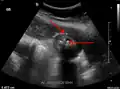

Abdominal ultrasonography showing gallstones, wall thickening and fluid around the gall bladder

Acute cholecystitis as seen on ultrasound. The closed arrow points to gallbladder wall thickening. Open arrow points to stones in the GB